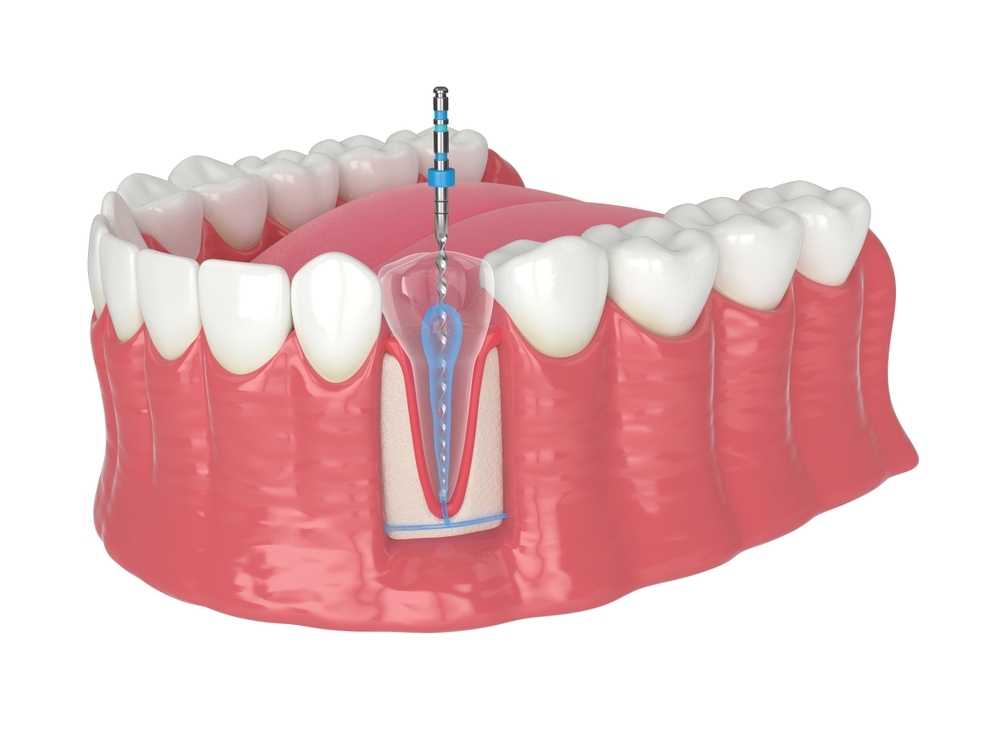

Rodbehandling

Læs mere